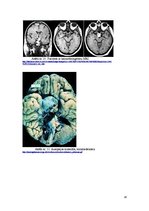

Klīniskā aina ir atkarīga no diviem patoloģenēzes faktoriem: no spiediena, kuru audzējs izdara uz apkārtējiem audiem un no tā hormonālālas aktivitātes. Taču salīdzinoši bieži ir sastopamas asimptomātiskas formas, kad audzēju atrod nejauši, citu iemeslu dēļ veicot galvas smadzeņu MRI vai CT. Galvenie simptomi ir galvassāpes, redzes traucējumi un endokrinopātijas.

Audzējam palielinoties izmērā viena no struktūrām, kura tiek piespiesta ir chiasma opticum, kas savukārt rada redzes lauka traucējumus – bitemporālo hemianopsiju, nospiežot redzes nervu var attīstīties – unilaterāla optiskā nerva atrofija, kontralaterāla hemianopsija. …